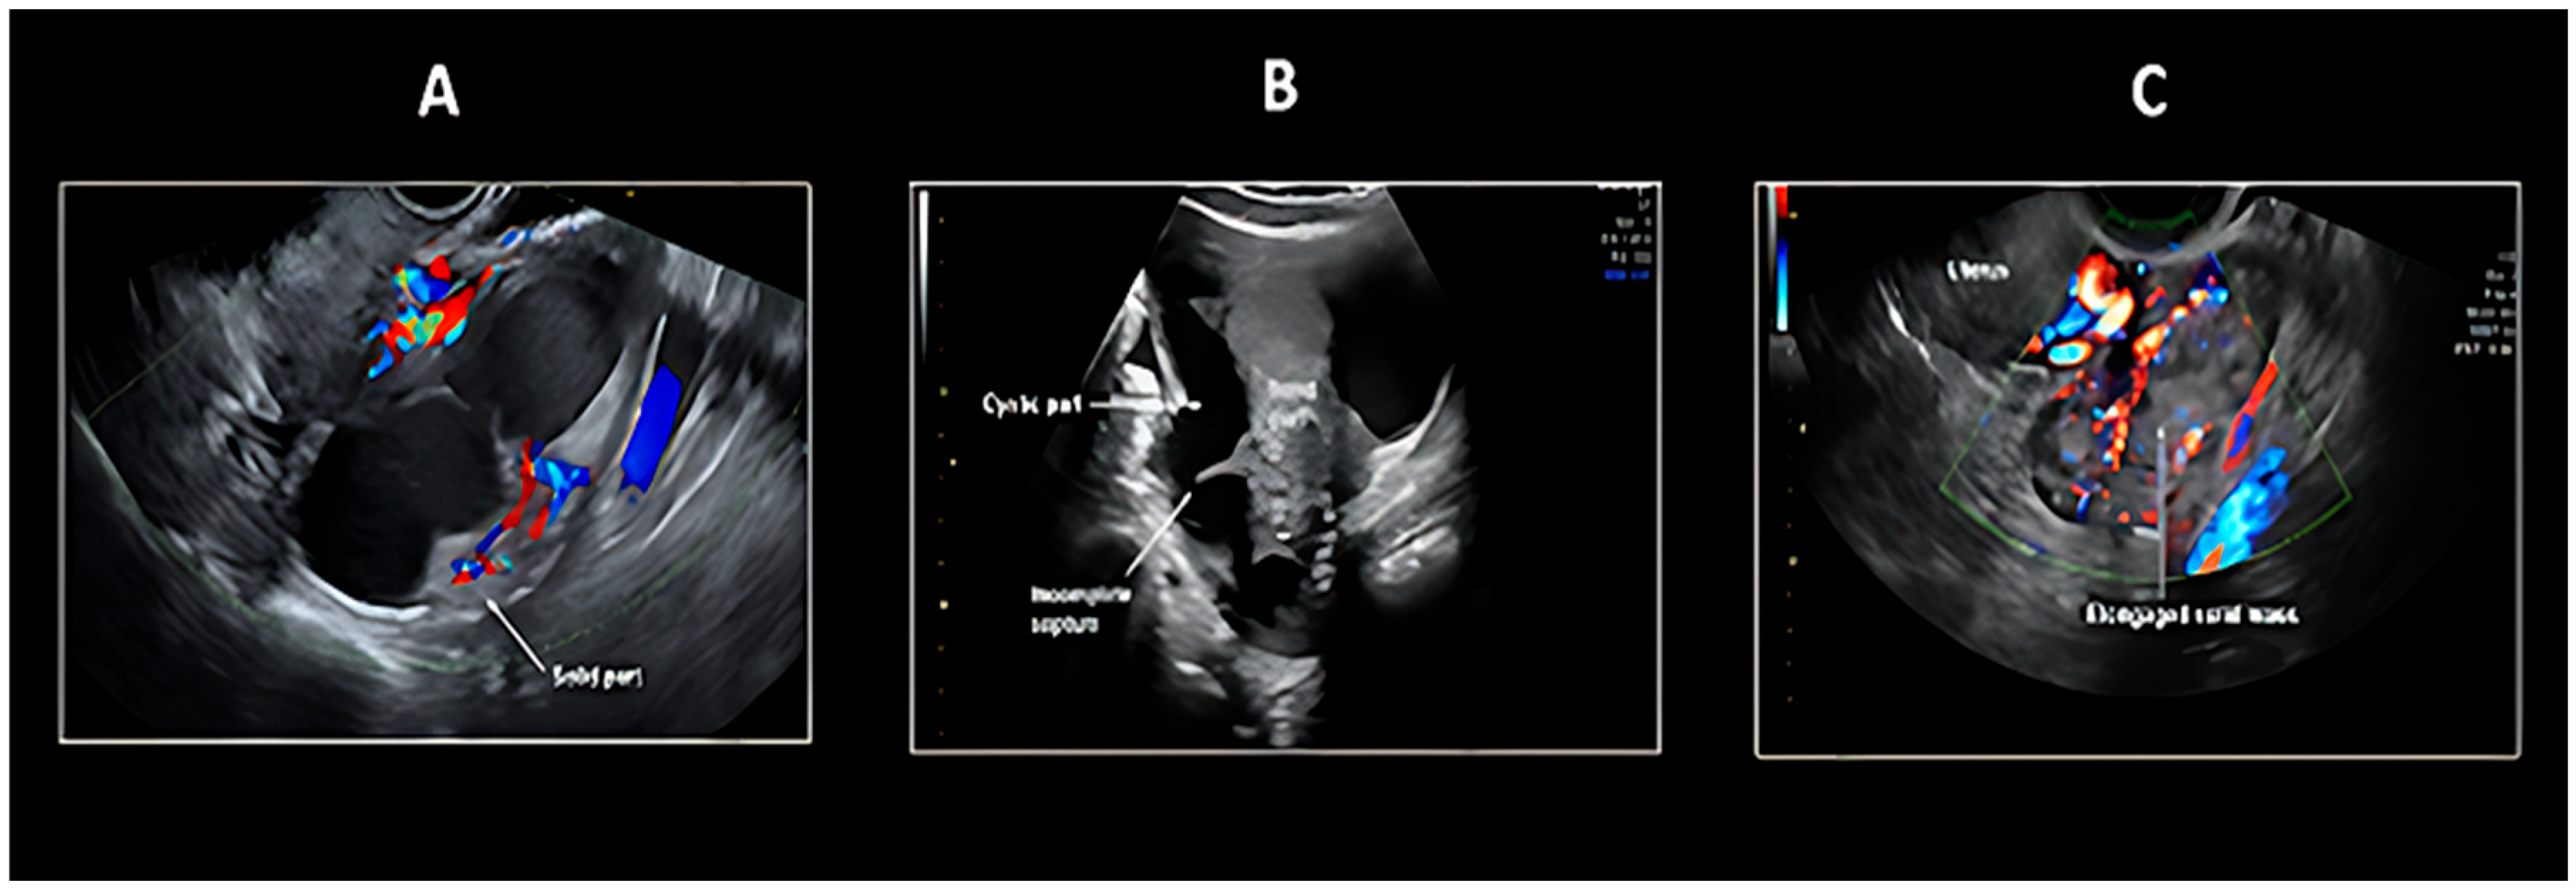

5.1. Transvaginal Ultrasonography

- Tongsong, T.; Wanapirak, C.; Tantipalakorn, C.; Tinnangwattana, D. Sonographic Diagnosis of Tubal Cancer with IOTA Simple Rules Plus Pattern Recognition. Asian Pac. J. Cancer Prev. APJCP 2017, 18, 3011–3015. [Google Scholar]

| Morphology | Tubular/sausage-shaped mass |

| Doppler Flow | Moderate vascularity in solid portions |